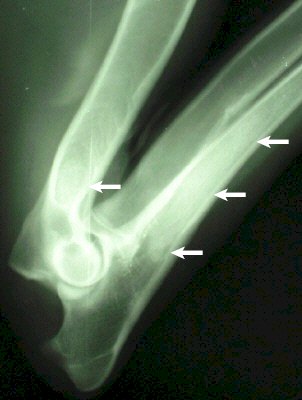

Röntgenbild: linke Vordergliedmaße

Weißer Schäfer - männlich - 10 Monate

Panostitis im Ober- und Unterarm

Deutscher Schäfer - weiblich - 7,5 Monate

hochgradige Panostitis im Oberarm